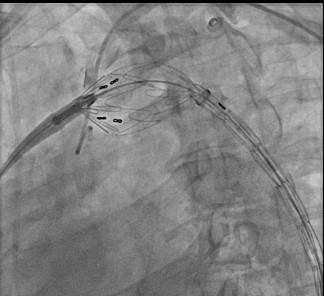

Left femoral artery was exposed & cannulated. Left radial artery access was done. Pigtail catheter was taken through the left radial access & aortography was done to confirm the location of aortic dissection.

A pigtail catheter was kept in the arch of the aorta for land mark. A guidewire was taken. Then the stent graft was positioned. 32x204 Valiant Thoracic Stent was chosen. It was placed in descending thoracic aorta from arch of the aorta just distal to left subclavian artery covering ruptured dissecting flap atthoracic aorta. After deployment, final aortogram showed ruptured segment of aortic dissection completely sealed with well visualised rest of the thoracic and abdominal aortaand its bifurcation to the lower limb arteries.